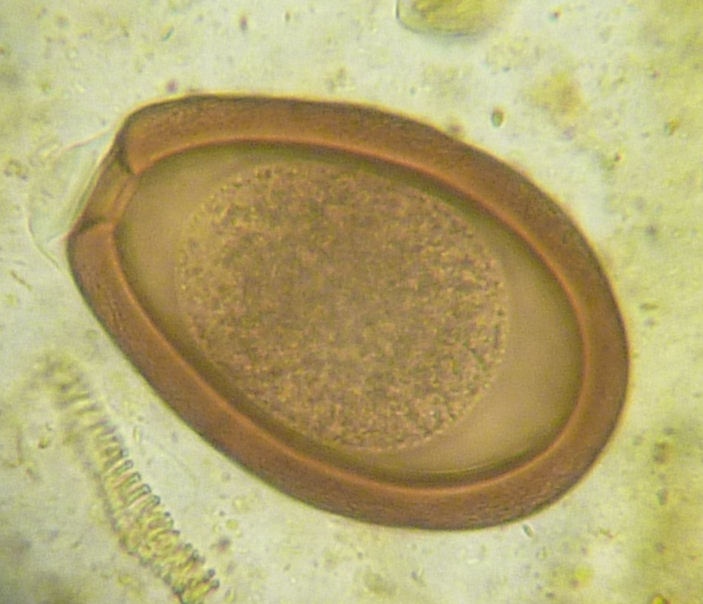

Наиболее часто встречающиеся у домашних птиц кокцидий принадлежат к роду Eimera. Виды Eimeria часто отличаются морфологией ооцисты, которая представляет собой толстостенную зиготу, распространяющуюся с пометом зараженного хозяина. Ооцисты заключены в толстую наружную оболочку и состоят из единственной клетки, запускающей процесс споруляции, в результате которого примерно через восемь часов образуются инвазивные ооцисты (рис.).

У видов Eimeria прямой цикл развития (рис. 1). Спорулированные ооцисты («яйца» паразитов) проникают в организм цыплят из инфицированного помета, после чего попадают в пищеварительный тракт, где паразиты проникают в клетки стенки кишечника.

Проходит несколько фаз развития, после которых образуются ооцисты, выводящиеся из организма с пометом. В зависимости от окружающих условий (в том числе температуры и влажности) ооцисты спорулируют и становятся заразны. Весь цикл занимает от 4 до 6 дней. Этот короткий прямой жизненный цикл в сочетании с потенциалом к массовой репликации на внутриклеточной стадии делает данную группу паразитов серьезной проблемой в условиях интенсивного птицеводства.